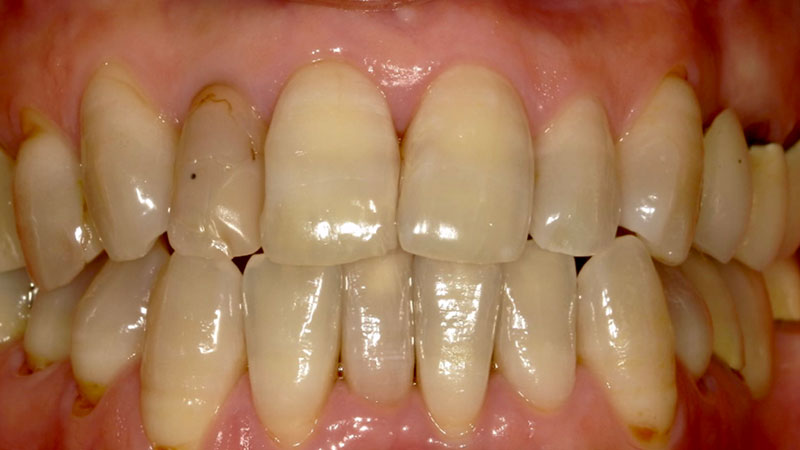

デュアルホワイトニング症例

デュアルホワイトニング症例をご紹介します。

デュアルホワイトニングとはオフィスとホームを併用する処置になります。

オフィスのいいところである短時間での漂白と、ホームのいいところである持続的な漂白が可能になります。

今回のように加齢で黄ばんだ頑固な着色も真っ白にできます。

加齢による歯の黄ばみはクリーニングだけでは綺麗になりません。

また、今回のように歯にまだら模様の変色がある場合はホワイトニングによって目立たなくなります。

| 患者様 | 70代女性 |

|---|---|

| 主訴 | 全体的な黄ばみが気になる |

| 治療費 | ベーシックコース77,000円(税込) ホームホワイトニング16,500円(税込) 総額93,500円(税込) |

| 治療期間 | オフィスホワイトニング8回 ホームホワイトニング1ヶ月 |